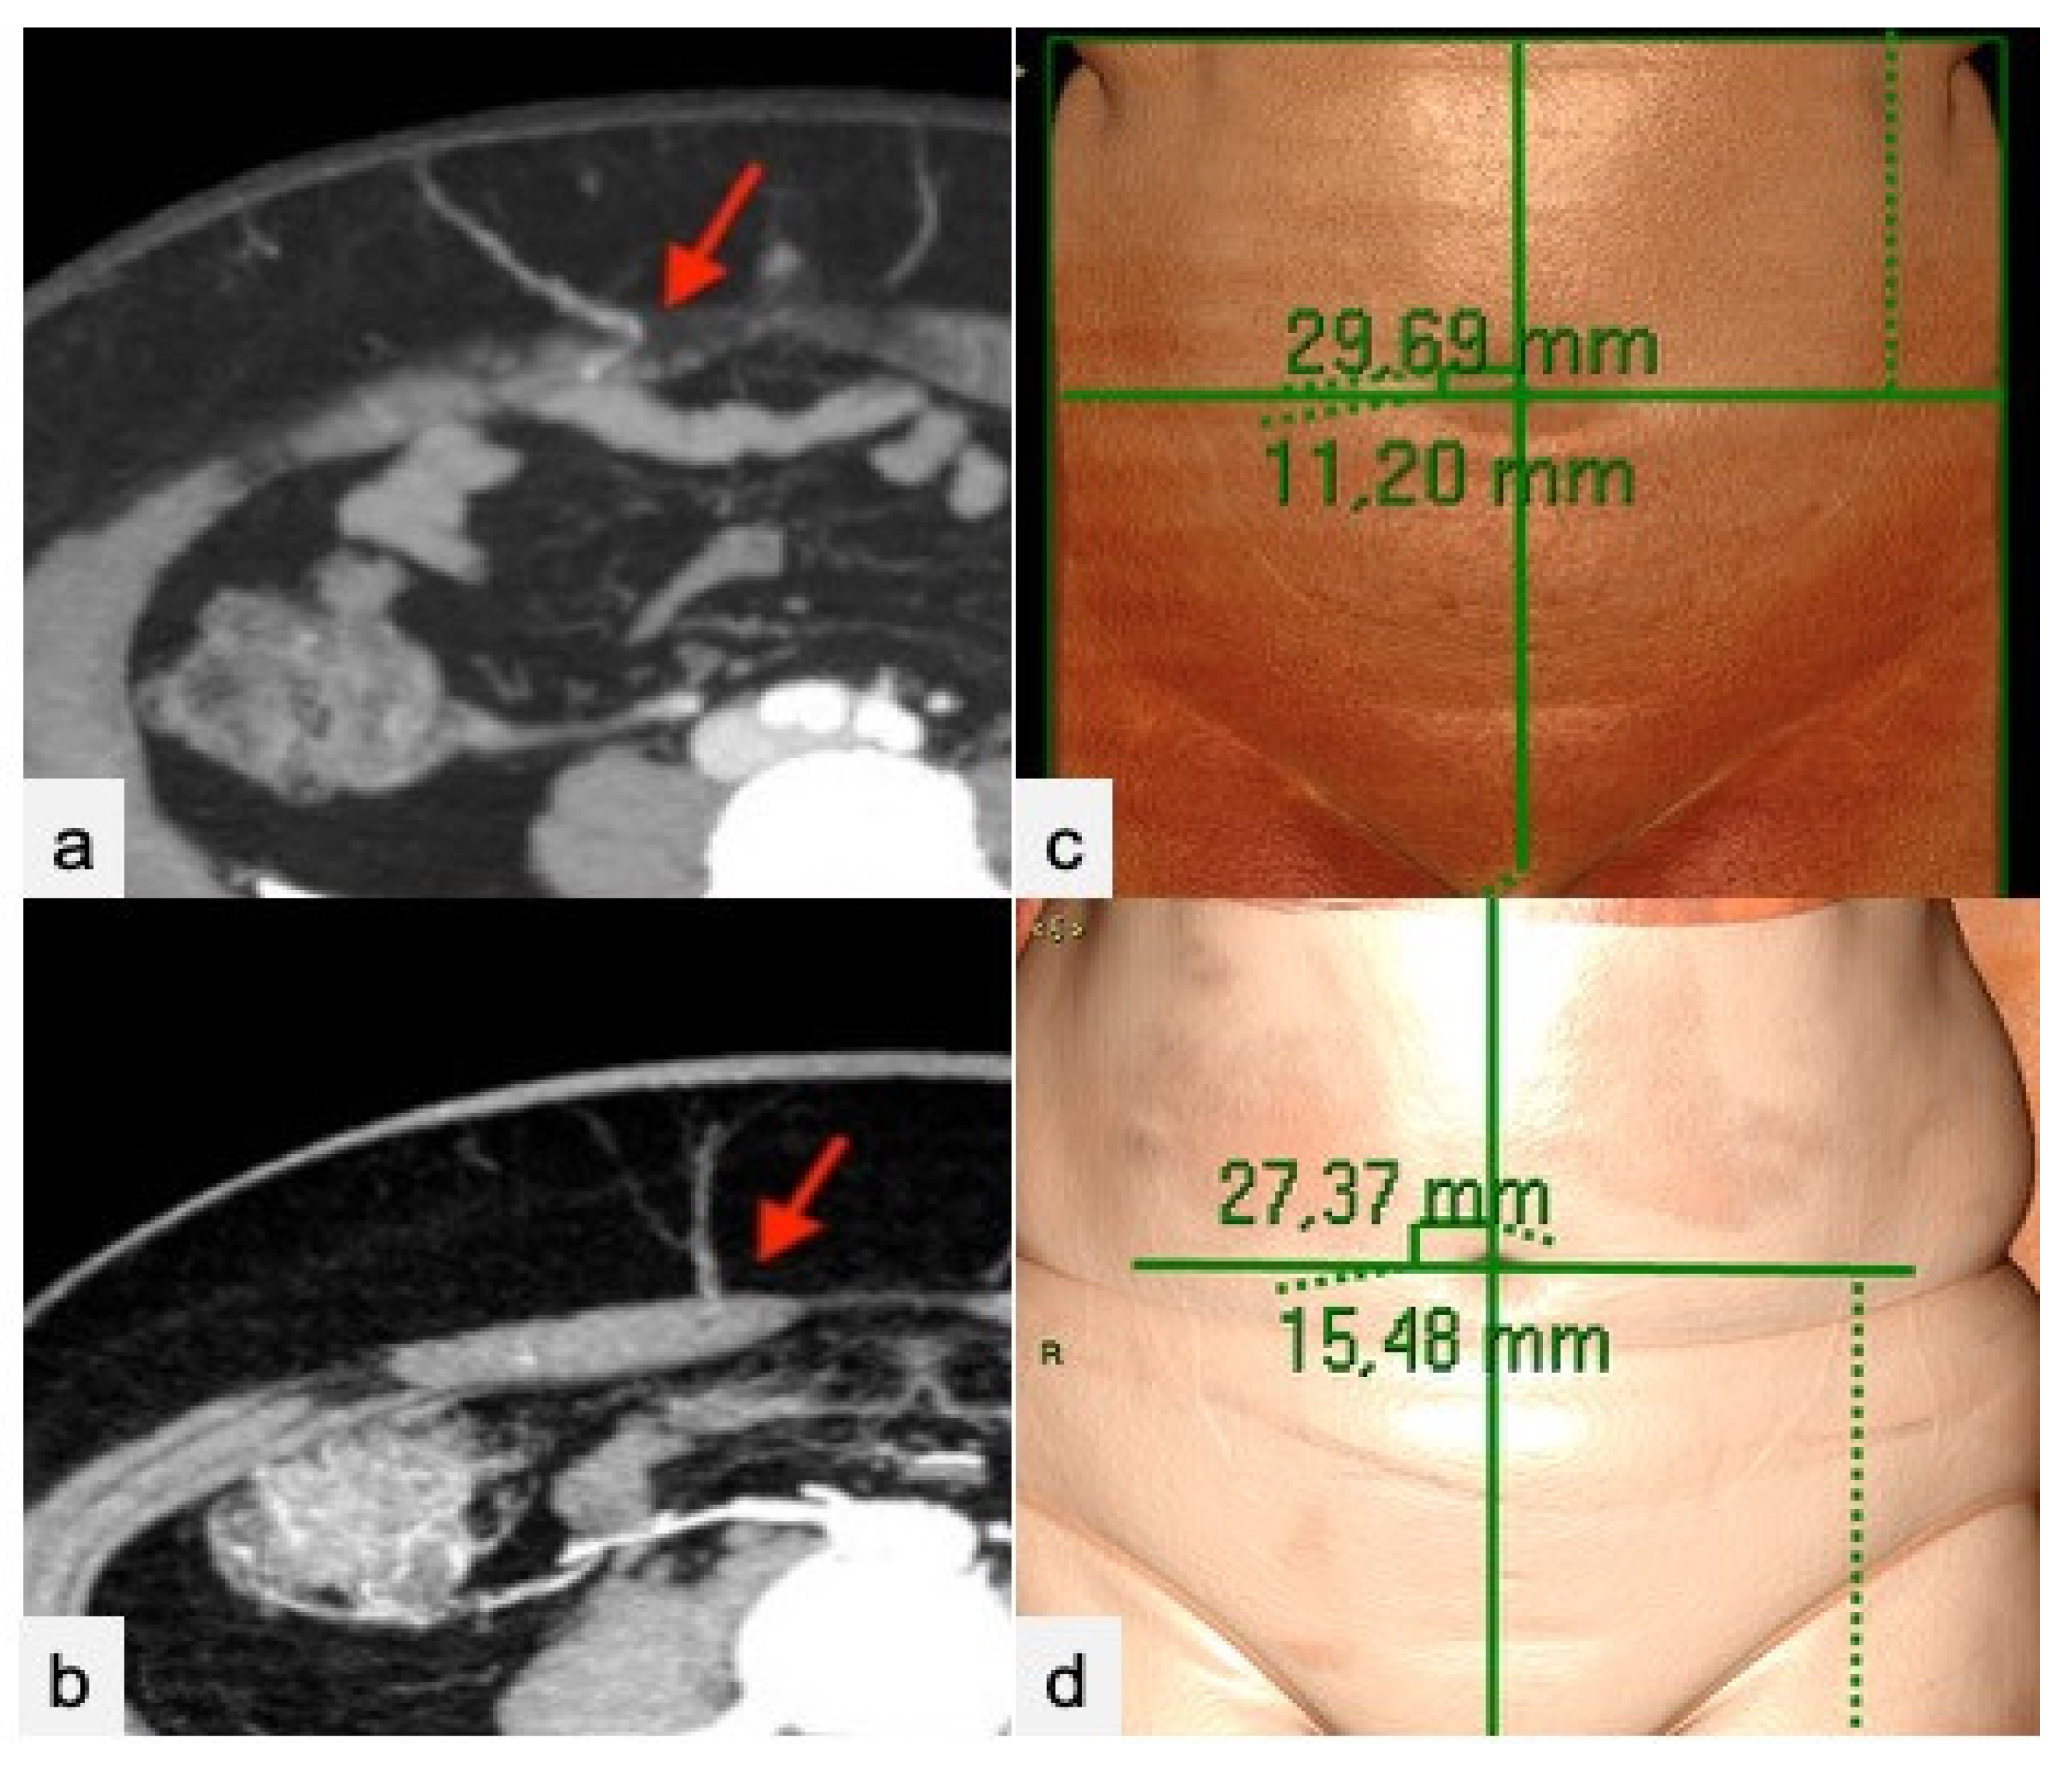

2. Materials and Methods

2.1. CTa and cCT Technique

2.2. Image Analysis

3. Results

4. Discussion